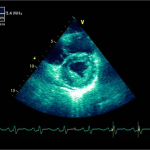

Ecocardiografia transtoracică

- Formaţiune hiperecogenă cu suprafaţa neregulată, care tapetează peretele liber al VD, grosime de 12 mm

- Dispusă de sub planul valvei tricuspide până in apropierea conului de ejecţie al valvei pulmonare

- SIV aplatizat

Ecografia transesofagiană:

Confirmă datele de la ecografia transtoracică